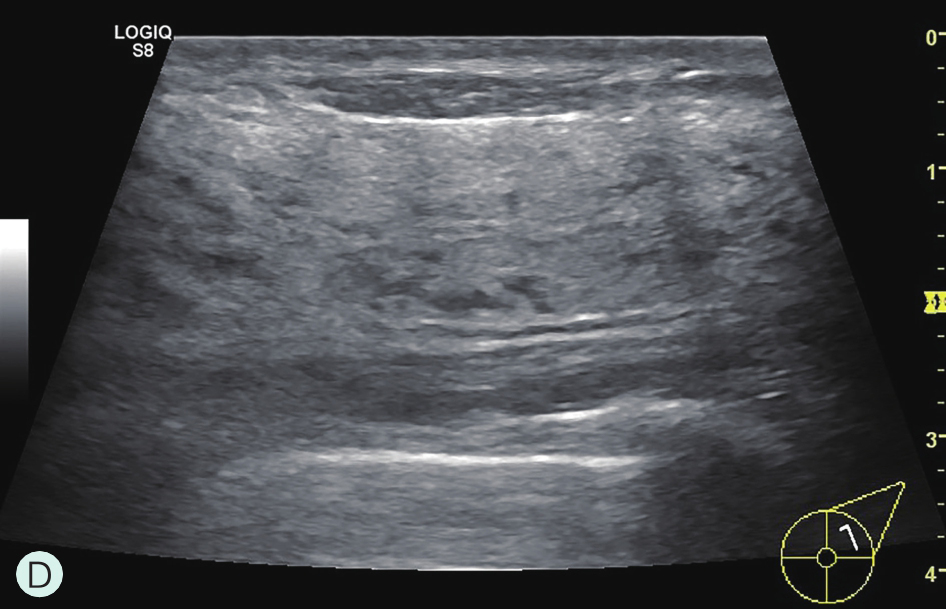

D级:极度致密型(降低乳腺钼靶摄影的敏感性)(图1-3-1D、图1-3-2D、图1-3-3D)。

图1-3-2 乳腺超声不同乳腺密度

A.脂肪型;B.散在致密型;C.不均匀致密型;D.极度致密型